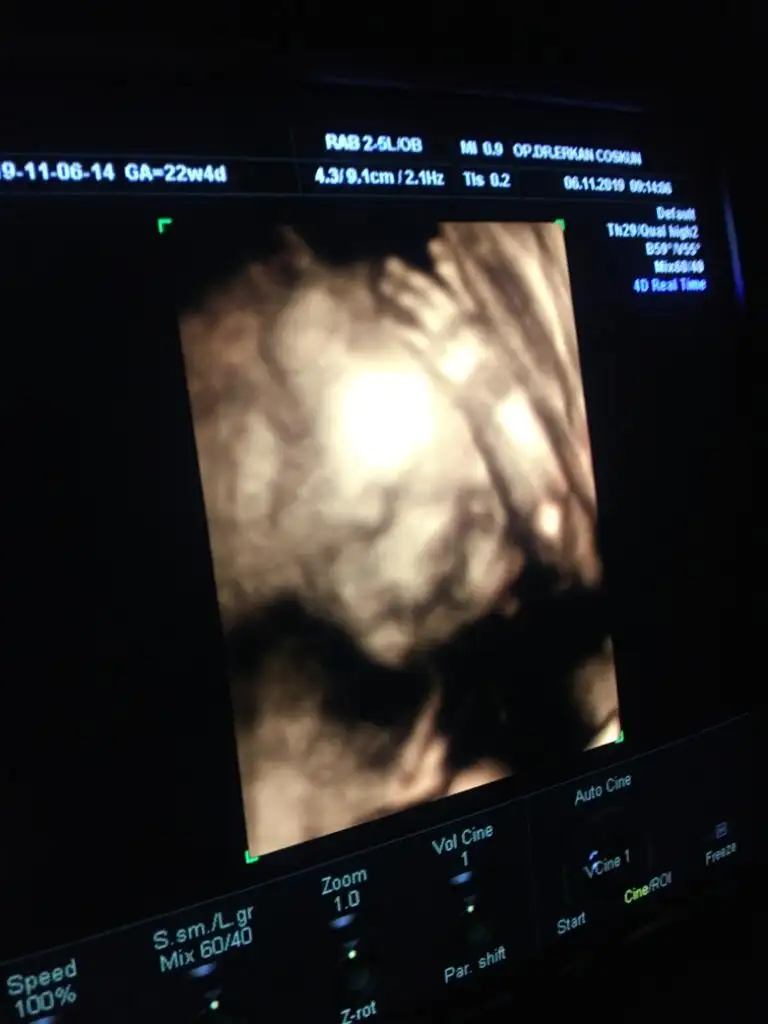

Canım buda benim bebeğimin fotoğrafı dudağı yarık gibi duruyor ama doktor böyle bir şey olsa farketmez miydi. Perinatolog birdekzılar mehaba 27 haftalık 4 boyutlu ultrason görüntüsü bu. bazı ultrasonlara bakıyorum acaba benim bebeğin burnunda sorun olabilir mi ? başkalarının ultrasonunda çok düzgün görünüyorlar

Canım buda benim bebeğimin fotoğrafı dudağı yarık gibi duruyor ama doktor böyle bir şey olsa farketmez miydi. Perinatolog birdecanım hiç merak etme tam o foto çekilirken hareket edince öyle cıkıyor benim de dudağı bi tuhaf cıkmıştı doktora sordum hareketli olduğu icin oluyor dedi normalde öyle değil merak etme dedi güldü

Merhaba , kızımda da aynı endişeyi yaşamıştık . Doktor ultrason görüntüsünden kaynaklı olduğunu söylemişti . Yani bebek suyun içinde ve hareket halinde , çekim hatası gibi düşün demişti. Doğdu herhangi bir sorun yok yarık dudak gibi . Sanırım şu ultrason görüntüsüydü bizi de şüpheye düşüren. Sen yine doktoruna sor bir dahaki kontroldeCanım buda benim bebeğimin fotoğrafı dudağı yarık gibi duruyor ama doktor böyle bir şey olsa farketmez miydi. Perinatolog birde

Sağlıklı doğdu yani sorcam insAllah orda hiç farketmemisim teşekkür ederimMerhaba , kızımda da aynı endişeyi yaşamıştık . Doktor ultrason görüntüsünden kaynaklı olduğunu söylemişti . Yani bebek suyun içinde ve hareket halinde , çekim hatası gibi düşün demişti. Doğdu herhangi bir sorun yok yarık dudak gibi . Sanırım şu ultrason görüntüsüydü bizi de şüpheye düşüren. Sen yine doktoruna sor bir dahaki kontrolde